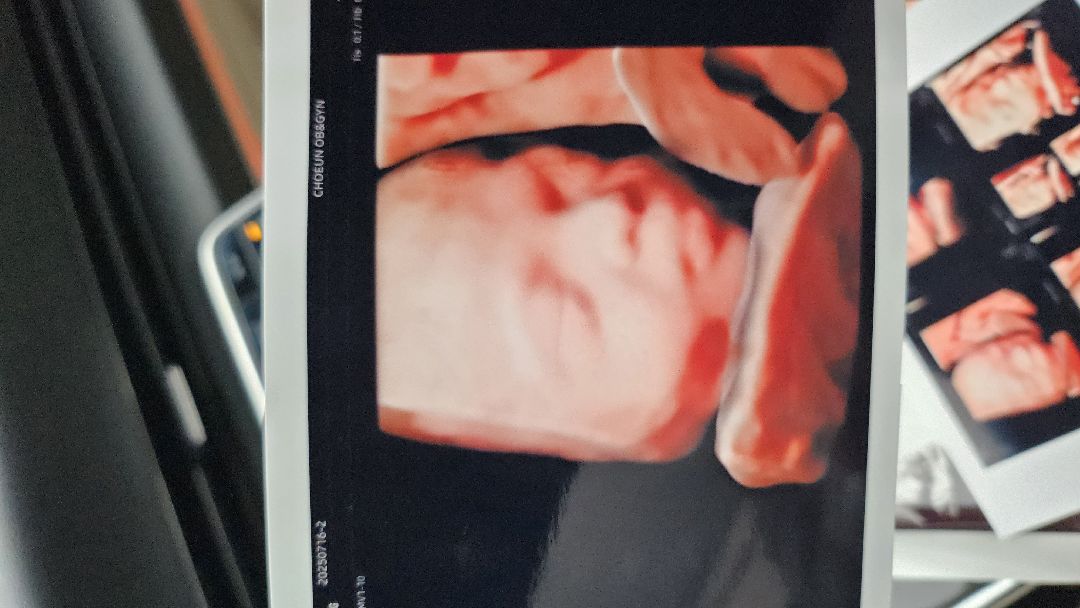

AI입체초음파

요즘 세상이 좋아졌네요... 작년 이맘때 연년생 딸 낳을때만해도 이런건 없었는데... Ai입체 초음파 짱짱!!

와 너무 신기해요! 얼굴이 좀 더 선명하고 명확히 보이네요^^